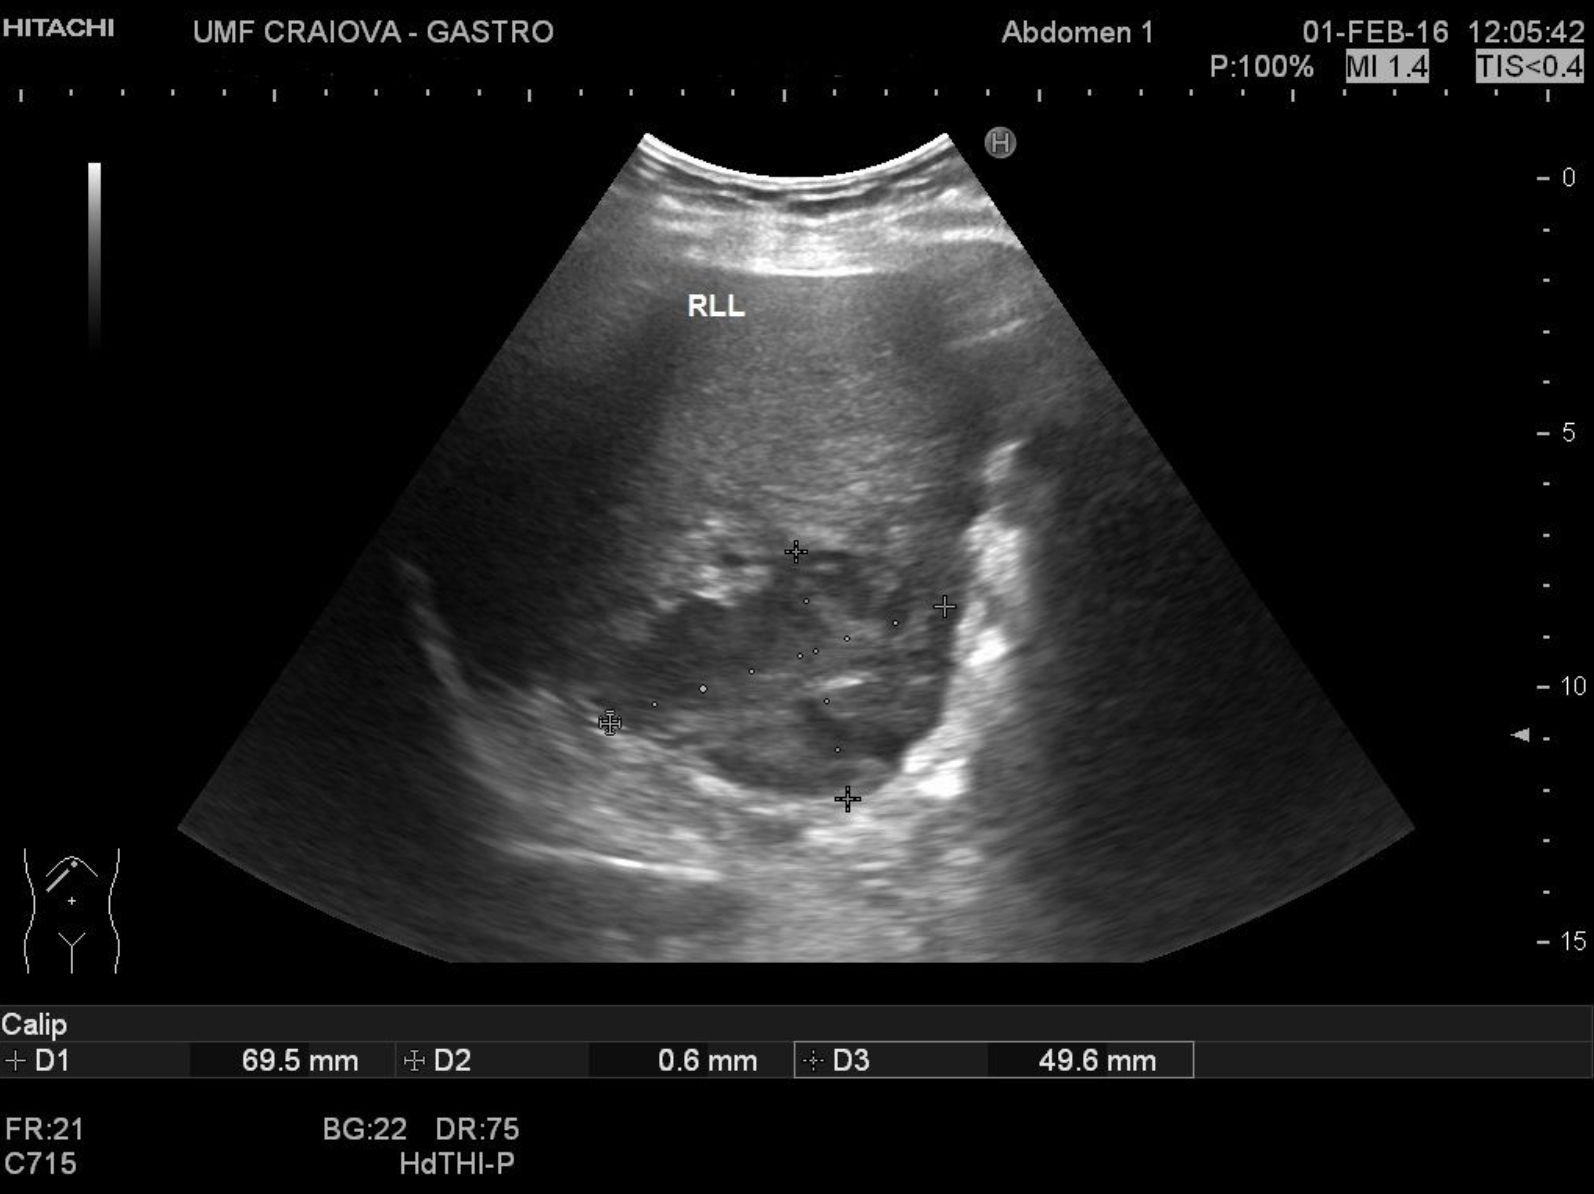

Liver abscess [1 image] Categories AbscessBASIC ULTRASOUND IMAGESLiver TITLE: Liver Abscess DESCRIPTION: An irregular hypoechoic mass in the caudate liver lobe EMAIL CONTACT:constantinescu.codruta@yahoo.com KEYWORDS:liver ultrasound, liver abscess Related postsJanuary 5, 2021Walled-off pancreatic necrosis [2 images]Read more